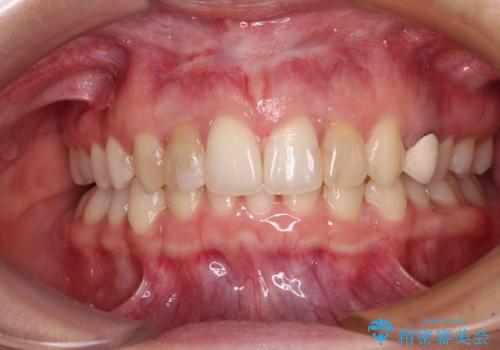

【モニター】前歯の変色とデコボコを改善 インビザラインとオールセラミック

- 前歯の歯並びと神経を取って変色してしまった前歯を気にして来院された患者様です。

上下前歯の歯列不正はインビザラインにより整え、その後に、前歯2本をオールセラミッククラウンにて補綴治療することとしました。